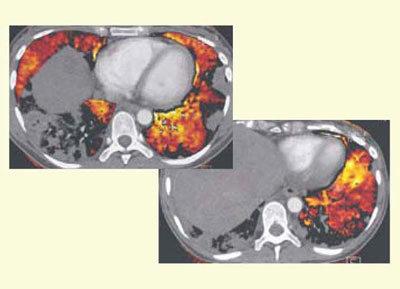

急性肺血栓塞栓症に対して,血栓溶解療法を施行し,その治療効果を前後のLungPBVによるCT値の計測を行って評価した。図5のように,両下肺野では発症時のLungPBVは,24HU,28HUから38HUに改善している一方で,上肺野は41HUから38HU,34HUに若干低下している。おそらく,発症時には上肺野で代償性過灌流が起こっていたのではないかと推察される。

図5 血栓溶解療法前後のLungPBVのCT値の変化

肝臓に多数の転移巣があり,下大動脈内にも腫瘍塞栓を来している子宮がん肝転移の症例で,発熱に伴いCTを撮影したが,両下葉主体に胸膜に沿って陰影が見られた。腫瘍塞栓が疑われるが肺炎との鑑別が難しく,LungPBVを行ったところ(図6),陰影周囲にくさび状の欠損像が見られ,腫瘍塞栓と診断できた。

図6 子宮がん,肝転移症例のLungPBV

LungPBVのくさび形の欠損像から腫瘍塞栓と診断された。